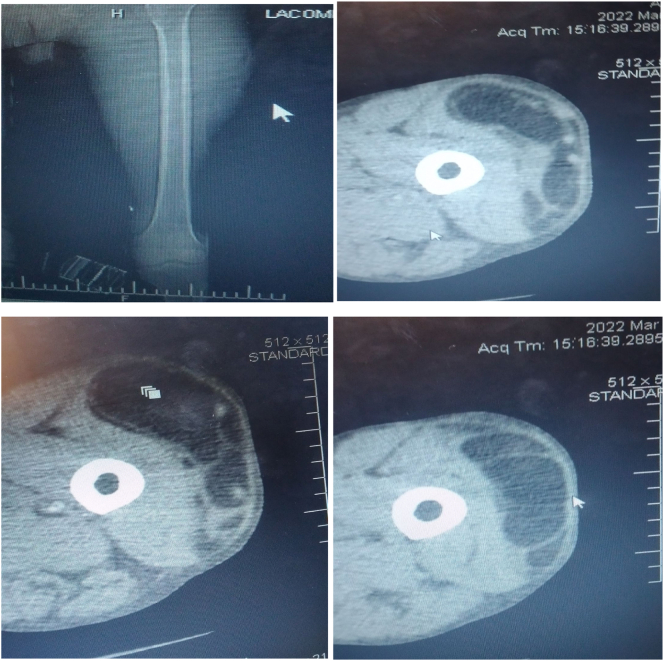

Objectively, he was comfortable with stable vital signs. There was no lymphadenopathy, chest was clear and resonant. There are two previous incision sites on left thigh. There was 20 × 60 cm non tender, soft to firm, slightly mobile swelling on left thigh spanning anterior, lateral and posterior compartment, no inguinal swelling. All blood work (complete blood count and organ function tests) were normal. Fine needle aspiration cytology from mass reported spindle cell tumor with mixed mesenchymal and fatty cells. Chest X-ray and abdominal ultrasound for metastasis were negative. CT-scan of chest, abdomen and pelvis for metastasis were free. CT-scan of the involved extremity showed 20 × 50 × 20 cm left thigh soft tissue mass involving anterior, lateral and posterior compartment extending from supra-knee area to mid of femoral triangle and up to gluteal region (10 cm below iliac crest) postero-laterally. There is no involvement of femoral vessels and there is no inguinal mass. Fine needle aspiration cytology from the mass reported sarcoma. CT-scan stated diagnosis as sarcomatous tumor (Fig. 1A-D).

Fig. 1.

A-D: Cross-sectional CT-images of the mass demonstrating hypodense lesion with heterogenous, irregular and septated lesion.